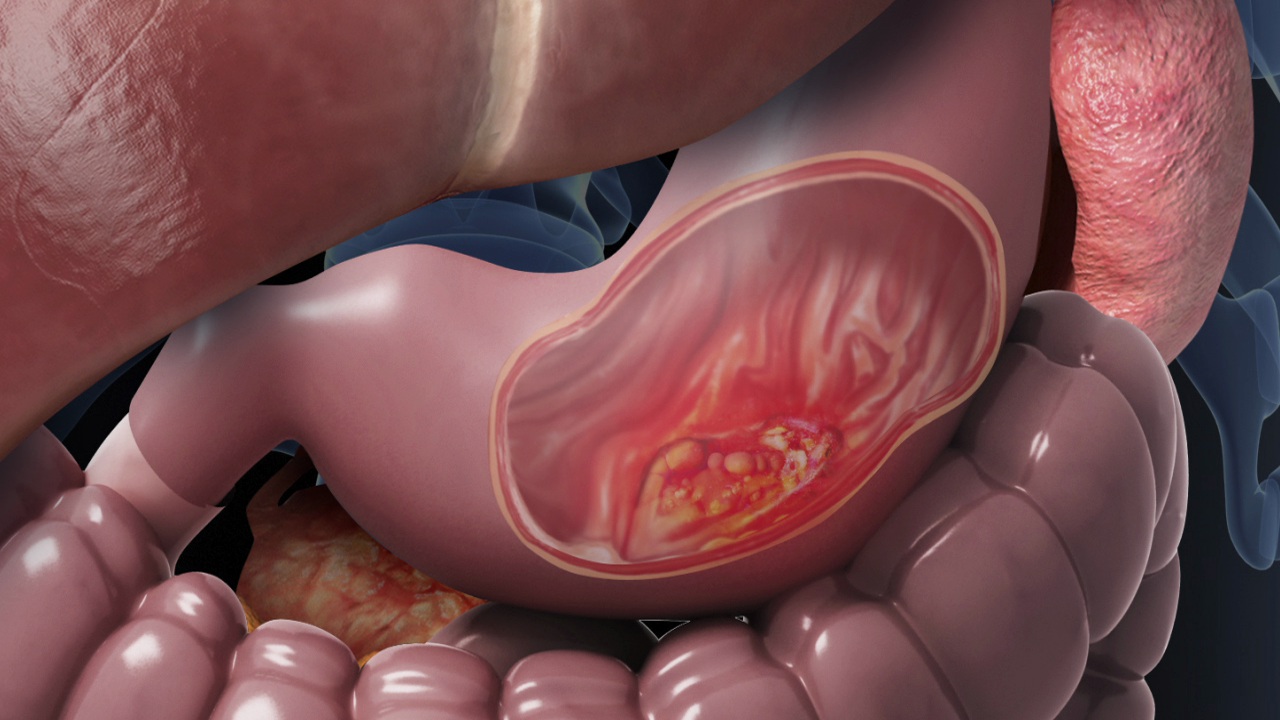

أعراض شلل المعدة الناتج عن ارتفاع السكر في الدم

يؤثر ارتفاع نسبة السكر في الدم على الجسم بعدة طرق ومن ضمنها التأثير على الجهاز الهضمي؛ حيث يمكن أن يتسبب في تلف الأعصاب وإبطاء عضلات الجهاز الهضمي أو عدم عملها على الإطلاق وهو ما يُعرف باسم شلل المعدة.

حالة شلل المعدة

ومن هنا لا تستطيع المعدة أن تفرغ بشكل صحيح الطعام المهضوم ويستغرق الأمر وقتًا طويلًا لمغادرة المعدة، وهي حالة تعرف باسم شلل المعدة، والتي تؤثر على كيفية نقل المعدة للطعام إلى الأمعاء، ما يؤدي إلى الانتفاخ والغثيان والحرقة.

وعندما يسبب مرض السكري هذه الحالة، يسميها الأطباء شلل المعدة السكري. ويُعرف شلل المعدة أيضا باسم تأخر إفراغ المعدة وهو اضطراب في الجهاز الهضمي يتسبب في بقاء الطعام في المعدة لفترة زمنية أطول من المتوسط.

ويحدث شلل المعدة بسبب تلف الأعصاب التي تنقل الطعام عبر الجهاز الهضمي، لذلك لا تعمل العضلات بشكل صحيح، ونتيجة لذلك، يبقى الطعام في المعدة غير مهضوم.

والنساء المصابات بداء السكري من النوع الثاني لديهن مخاطر عالية للإصابة بشلل المعدة وكذلك أولئك الذين لديهم مستويات عالية من السكر في الدم غير المنضبط على مدى فترة طويلة من الزمن.

ويمكن لفترات طويلة من ارتفاع الجلوكوز في الدم أن تسبب تلف الأعصاب في جميع أنحاء الجسم.

ويؤدي ارتفاع مستويات السكر في الدم بشكل مزمن أيضا إلى تلف الأوعية الدموية التي تزود أعصاب وأعضاء الجسم بالتغذية والأكسجين، بما في ذلك العصب المبهم والجهاز الهضمي، وكلاهما يؤدي في النهاية إلى شلل المعدة.

ويوصف شلل المعدة بأنه حالة مزمنة يمكن أن تشعر عند الإصابة بها بالإرهاق، وتمثل الحالة مشاكل كبيرة لمرضى السكري لأن التأخير في الهضم يجعل التحكم في نسبة الجلوكوز في الدم أمرًا صعبًا.

ويجعل شلل المعدة عملية الهضم صعبة التتبع، لذلك يمكن أن تتقلب قراءات الجلوكوز.

وينصح خبراء الصحة إذا كنت تعاني من قراءات غير منتظمة للجلوكوز، تحدث مع أخصائي الرعاية الصحية الخاص بك مع أي أعراض أخرى قد تواجهها.

أعراض شلل المعدة

وبالإضافة للقيء والغثيان من الممكن أن تظهر أعراض أخرى لهذا الاضطراب تشمل: الشعور المبكر بالشبع، وانتفاخ في المعدة، وارتجاع في العصارة الهضمية إلى المريء ما ينتج عنه حرقة في فم المعدة، جنيا إلى جنب مع تغيرات في نسبة السكر في الدم، وفقدان الشهية، ونقص الوزن وسوء التغذية، بحسب موقع Express.